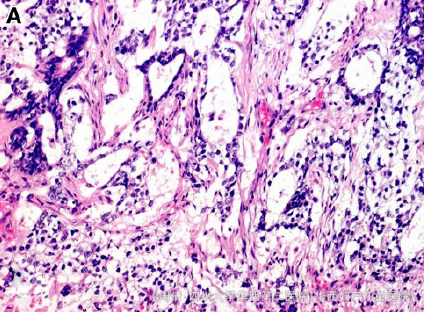

除AFP 5321ng/ml外,其余血液生化指标正常 超声提示阴道内有一肿瘤 MRI提示肿块大小3*4.5*3cm,分叶状,异质性 行活检,病理提示成片的立方形细胞排列成腺样结构,周围有疏松的粘液基质 免疫组化提示CK(AE1/AE3)强阳性 免疫组化提示AFP局灶阳性